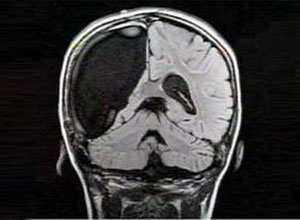

在卒中急性期是否应该进行降压治疗?(Stroke. 2012…

1小时0条评论题目:急性卒中血压变化与早期不良事件的风险和预后不良的关系(Relation Between Change in Blood Pressure in Acute Stroke and Risk of Early Adverse Events and Poor Outcome) 背景与目的:斯堪的纳维亚坎地沙坦急性卒中试验(SCAST)发现坎地沙坦对急性卒中...